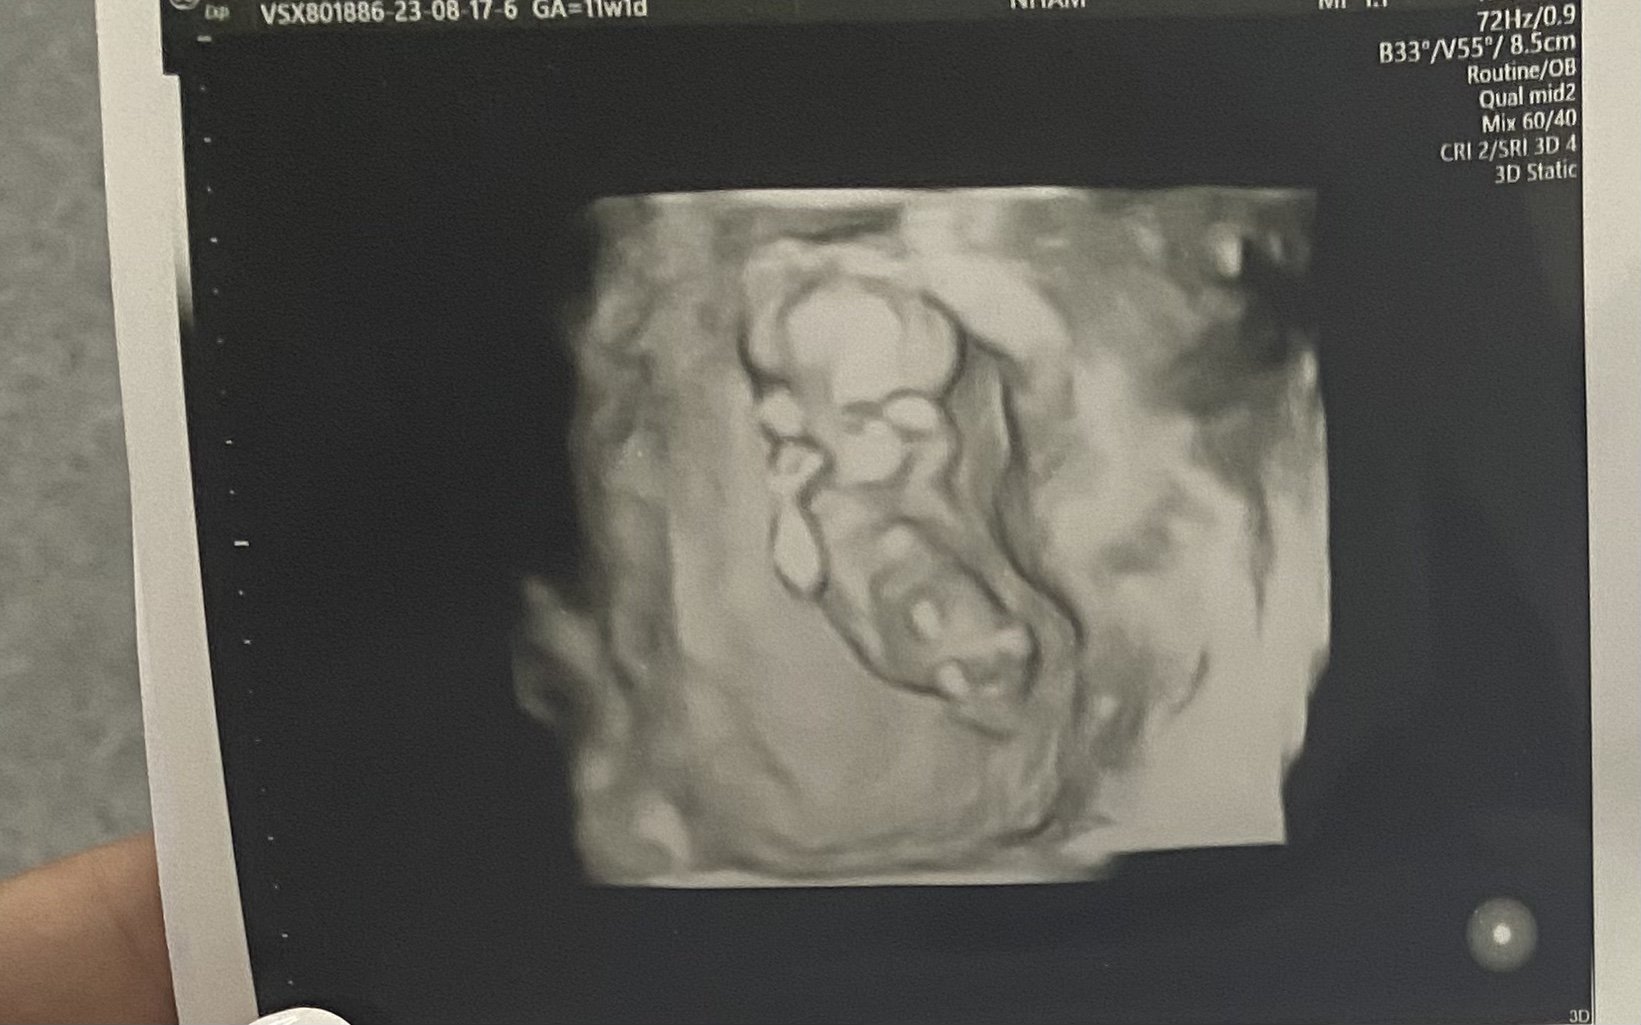

Какви са резултатите от изследванията и прегледите в ранна бременност?